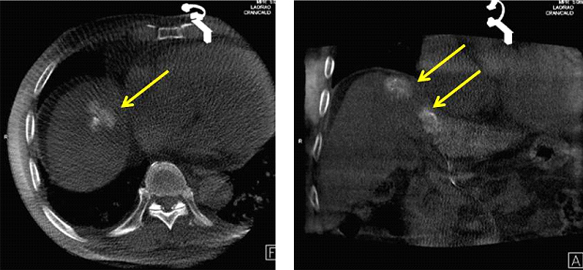

治療後にCTのような画像を撮影して、きちんと肝臓がんのところにだけに塞栓物質を詰めれているか(*白い部分が塞栓した部分です)が確認できます